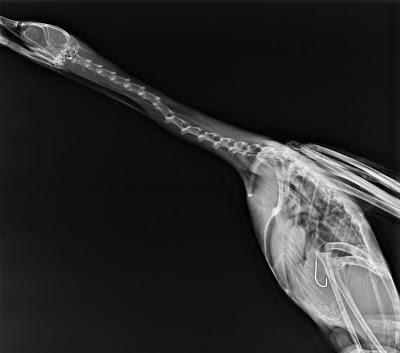

El cormorán del que podéis ver su radiografía fue recogido en la playa de Bañugues en agosto de este año mientras luchaba por soltarse de un palangre. Se lo había tragado pensando que era un pez inofensivo, quizás demasiado fácil de capturar. Mientras subía la marea, ya con el anzuelo clavado en el estómago, se le hacía cada vez más difícil mantenerse en la superficie para poder respirar. Y a cada intento de soltarse, el anzuelo se clavaba más y más profundo mientras iba desgarrándolo por dentro.

Afortunadamente pudo ser rescatado antes de morir ahogado, pero el anzuelo se le había clavado tan profundo que los veterinarios no fueron capaces de sacárselo por temor a producirle más lesiones que las que ya tenía. Se tuvieron que limitar a cortar el sedal lo más abajo posible y a confiar en que se pudiera recuperar.